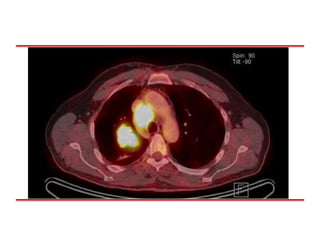

PET CT: 09/16

Lesión Broncogénica 1ª

LN Mediastinico, Hiliar,

Cervical, Implante Pleural.

Compromiso oseo.

• #6 Masa pulmonar central en el lóbulo superior derecho compatible con lesión broncogénica primaria. Conglomerados adenopáticos mediastínicos, hiliar y cervical bajo derechos, implante pleural ipsilateral y compromiso óseo multifocal secundarios. Nódulo retroperitoneal en fosa ilíaca izquierda sospechoso de localización secundaria. Nódulo pulmonar en el lóbulo superior izquierdo, bajo la resolución del estudio PET